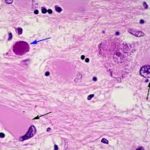

Immagine: topi telomerasi/deficienti subiscono un accorciamento dei telomeri e quindi non sono in grado di rigenerare il tessuto cardiaco danneggiato, anche solo dopo un giorno di vita. Il tessuto cardiaco telomerasi-deficienei (a destra) ha grandi regioni fibrotiche (blu) rispetto al wild-type del miocardio (a sinistra). Credit: Aix et al ., 2016

Topi telomerasi/deficienti hanno telomeri più corti rispetto a topi normali ed i ricercatori hanno anche scoperto che i cardiomiociti smettono di proliferare il giorno dopo la nascita. Quando Flores e colleghi hanno causato danni al cuore di vecchi topi, i cardiomiociti telomerasi-deficienti, non sono riusciti a proliferare o rigenerare il miocardio danneggiato.